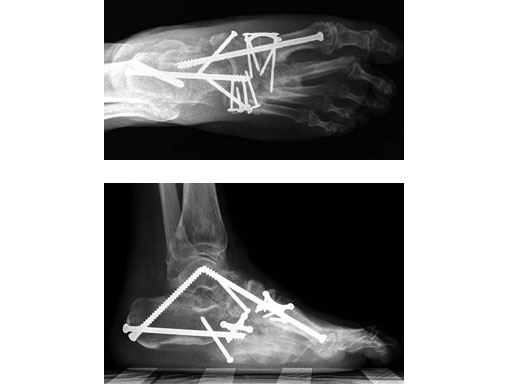

Case 2: 48-year-old male

Case provided by Andrew K Sands, New York, USA

Charcot foot treated with MFB and X-plate.